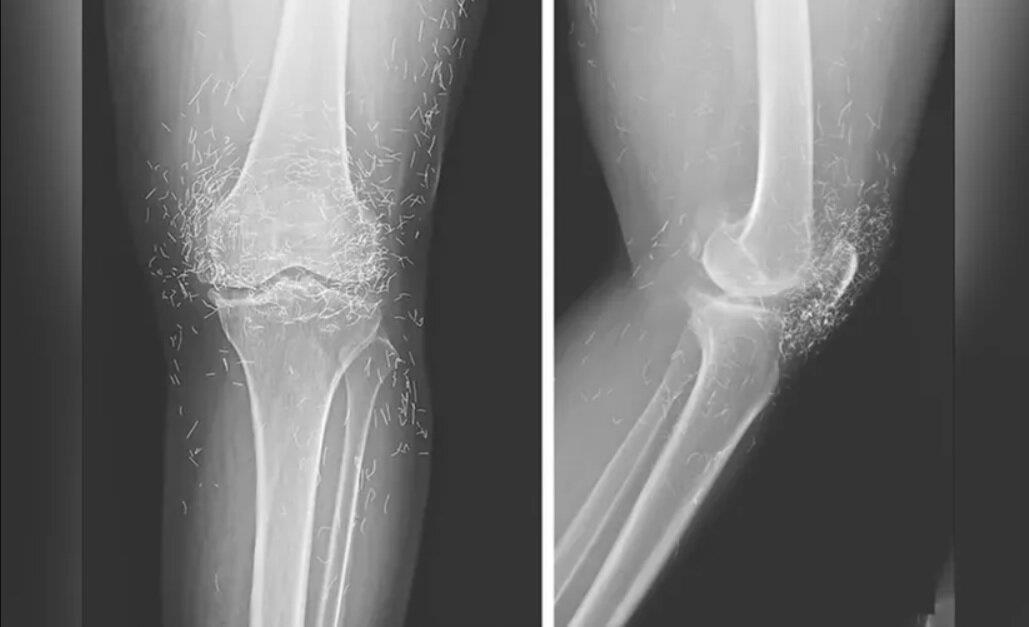

اما این روش هم نهتنها دردی از این زن دوا نکرد، بلکه زانودرد او را هم شدت بخشید. درنهایت او مجبور شد دوباره به بیمارستان مراجعه کند و پزشکان هنگام تصویربرداری از زانوها و دستهای او متوجه صدها رشته ریز و نازک از طلا در بافتهای اطراف زانو و دستهای این زن شدند.

طب سوزنی با رشتههای طلا در برخی از کشورهای آسیایی، بهویژه میان سالمندان، رایج است اما پزشکان هشدار دادند این روش هیچ پشتوانه علمی ندارد و حتی ممکن است موجب عوارض خطرناکی چون ایجاد کیست، جابهجایی نخها در بدن، آسیب به بافتها و حتی اشکال در انجام تصویربرداری MRI شود.